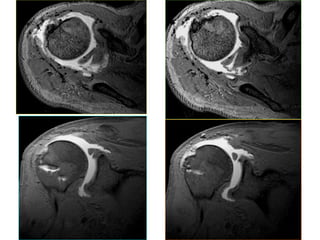

MRI KHÔÙP VAI

MRI arthrography

- MRI laø phương tieän quan troïng, höõu ích

trong chaån ñoaùn caùc toån thöông vuøng vai.

- MR Arthrography laø KT khaûo saùt thöông

toån khôùp vai hieäu quaû, phoå bieán hieän nay

treân theá giôùi.

- 1992, Traughber và Goodwin :

MRI kinh điển / rách bán phần gân cơ chóp

xoay (có kiểm chứng bằng nội soi khớp) : ñoä

nhaïy laø 56-72%, ñoä ñaëc hieäu là 83-85%.

- William B. Stetson:

Độ nhạy của MR Arthro. / rách bán phần

chóp xoay là 91%. Điều này cũng được

khẳng định qua nhiều tác giả hàng đầu về

khớp vai và MRI xương khớp như Joe Bush,

Joel Lipman và David Stoller